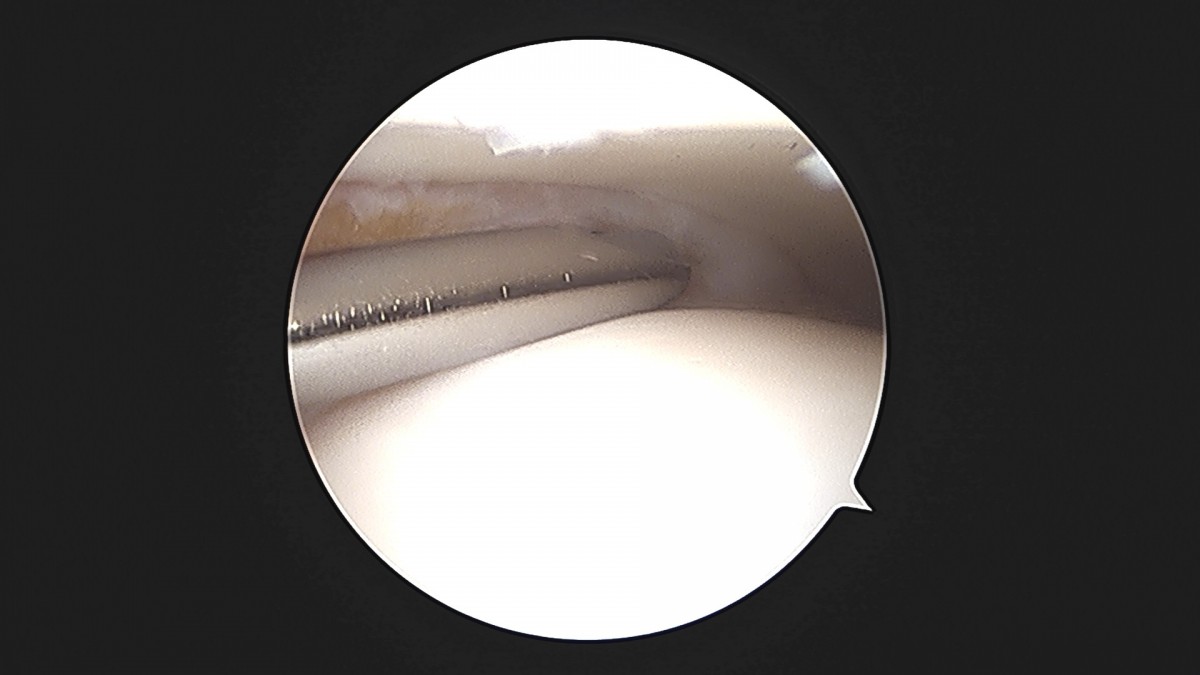

이재상원장님 발목 활액막 절제술 및 인대 봉합술 이승O 환자

작성자 최고관리자 댓글 0건 조회 787회 작성일 25-09-16 15:24